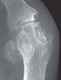

If the joint can be aspirated, presence of synovial fluid urate crystals on microscopy confirms the diagnosis with 100% confidence (see figure 3).23